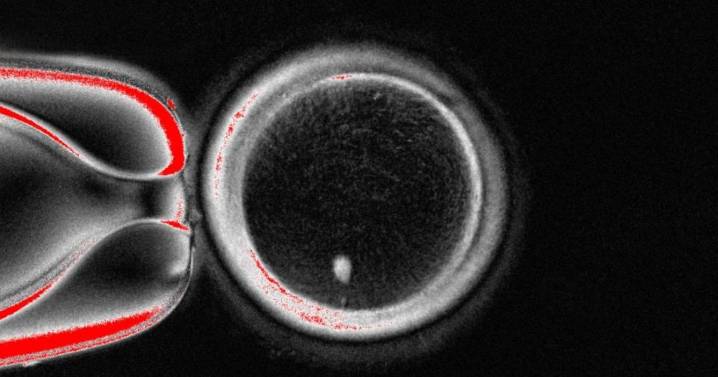

Ovocito con una imagen brillante del núcleo de una célula cutánea antes de la fecundación Universidad de Salud y Ciencias de Oregón

Un estudio publicado en Nature muestra que las células de la piel humana pueden emplearse para generar óvulos con capacidad potencial de ser fecundados. La investigación, que introduce una técnica innovadora, aún requiere pruebas adicionales para confirmar su seguridad y eficacia antes de plantear aplicaciones clínicas.

El trabajo fue dirigido por Shoukhrat Mitalipov, de la Universidad de Salud y Ciencias de Oregón (EE.UU.), y constituye una prueba de concepto sobre cómo la reprogramación celular en humanos podría ofr